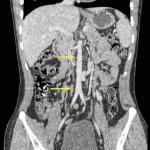

Cystite emphysémateuse

Une patiente de 89 ans, sans antécédent majeur, consulte aux urgences à la suite d’une chute accidentelle avec fracture...